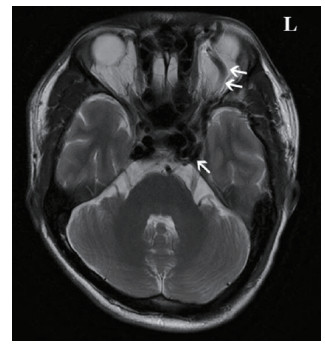

2.1 临床表现本研究中CCF患者出现眼球突出141例(97.91%)、球结膜充血140例(97.22%)、颅鸣105例(72.92%)、视力下降99例(68.75%)以及复视36例(25.00%)症状,见图 1。查体可见眼球突出、球结膜充血水肿,眼球运动障碍;眶周可闻及血管杂音,Matas试验阳性。脑部血管影像学检查,全部患者可见眼部静脉异常增粗[8],见图 2。

| 图 2 双箭头显示了异常增粗的左侧眼上静脉,单箭头处显示了扩张的海绵窦 Fig 2 Double arrows show abnormally thickened left superior ophthalmic vein, single arrow shows dilated cavernous sinus |